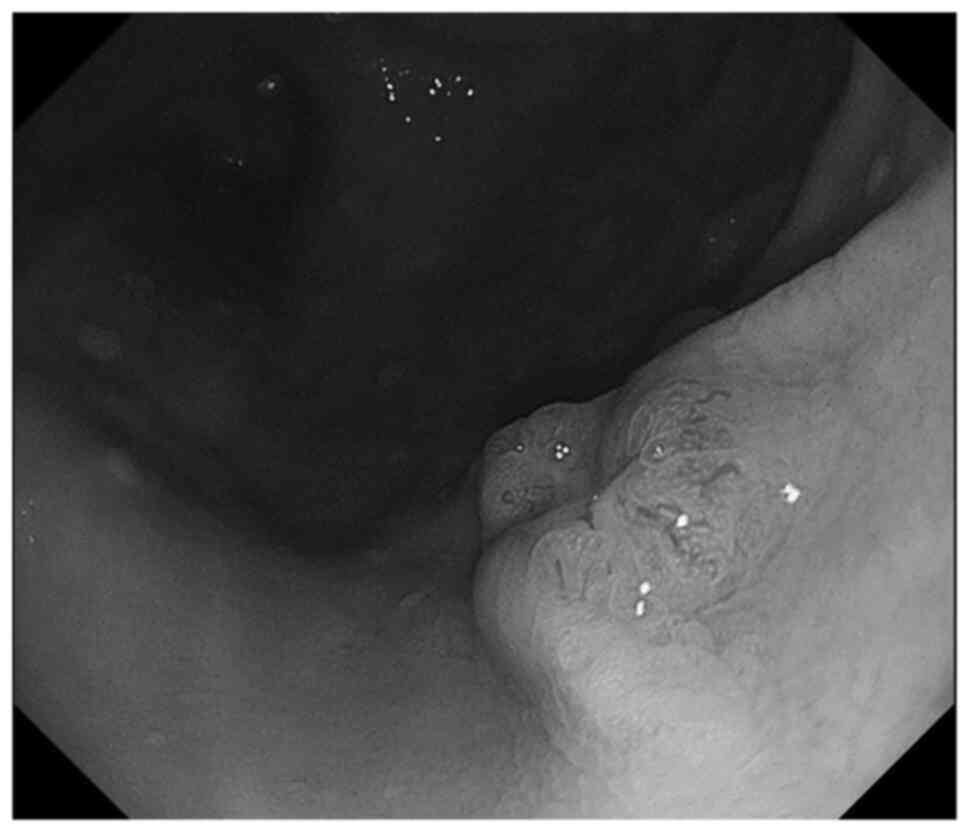

A 59-year-old woman visited Mie University hospital on January, 2013 due to a painless mass on her right thigh. After a needle biopsy was performed and she was diagnosed with LMS, she was subsequently referred to Mie University hospital. A physical examination and computed tomography (CT) confirmed a mass with a diameter of 5 cm on the postero-lateral side of the right thigh (Fig. 1). CT of the chest, abdomen and pelvis did not demonstrate any distant metastases. Wide resection of the tumor was performed. Tissue was fixed in 10% neutral-buffered formalin, embedded in paraffin. Tissue sections were sliced at 4 µm thickness, and stained with hematoxylin and eosin. Histological analysis using light microscope showed the proliferation of spindle cells with pleomorphic nuclei. The cells were set in long intersecting fascicles parallel and perpendicular to the plane of the section. Immunohistochemically, the tumor was positive for α-smooth muscle actin, desmin, and HHF35, but negative for S100 (Table I), which was consistent with the findings of LMS (Figs. 2A and B, and 3). After 1 year, she developed lung and bone metastases. Therefore, systemic chemotherapy using doxorubicin and ifosfamide was administered. Radiofrequency ablation (RFA) was performed for multiple bilateral pulmonary metastases. The bone metastasis was located in the mid-shaft of the femur. Cryoablation, curettage, and fixation with plate and cementation were performed to prevent fracturing. A total of 3 years after the initial surgery, she developed a bone metastasis in the right sixth rib. A resection of the sixth rib combined with resection of the fifth and seventh rib, to acquire a wide surgical margin was performed. A total of 5 years after the surgery, the patient developed sacral and skull bone metastases; thus, 11 cycles of trabectedin plus radiotherapy was prescribed. RFA was performed for residual multiple bilateral pulmonary metastases. After 6 years, abdominal CT revealed pancreatic metastasis. Therefore, eribulin treatment was administered. After 9 years, the patient was admitted to the general hospital for melaena. A submucosal tumor with central erosion was identified in the stomach by endoscopy, and a biopsy was performed (Fig. 4). The histological findings were consistent with a diagnosis of LMS. On CT, the gastric metastatic tumor was not detected, and the size of the metastatic mass in the pancreas was found to be gradually increasing (Fig. 5). The resection ability of both pancreatic and gastric metastatic tumors was discussed with a multidisciplinary team, and laparoscopic distal pancreatectomy and splenectomy, with partial gastrectomy, were performed. Subsequent histopathological examination confirmed metastasis of the LMS (Fig. 2C). At the final follow-up, 6 months after the gastrectomy (10 years from initial treatment), systemic chemotherapy was administered for residual pulmonary nodules.

Figure 4

Gastroscopy showing a submucosal tumor with central erosion in the anterior upper body of the stomach (Case 2).